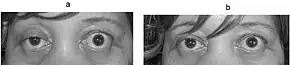

Photograph of a person showing right partial ptosis (left picture), the left lid shows compensatory pseudo lid retraction because of equal innervation of the levator palpabrae superioris (Hering's law of equal innervation): Right picture: after an edrophonium test, note the improvement in ptosis.

Edrophonium test

This test requires the intravenous administration of edrophonium chloride or neostigmine, drugs that block the breakdown of acetylcholine by cholinesterase (acetylcholinesterase inhibitors).[36] This test is no longer typically performed, as its use can lead to life-threatening bradycardia (slow heart rate) which requires immediate emergency attention.[37] Production of edrophonium was discontinued in 2008.[18]